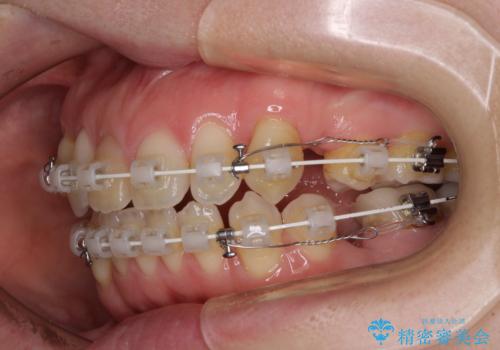

- 矯正装置

- 審美装置

上顎左右第一小臼歯2本、下顎左右第二小臼歯2本を抜歯し、ワイヤー装置にて口元を引っ込めるよう矯正治療を行うこととしました。

上下の前歯に隙間が空くほど上顎前歯が前に飛び出していましたが、抜歯矯正により上下前歯がぴったりと付くほど口元を引っ込めることができました。